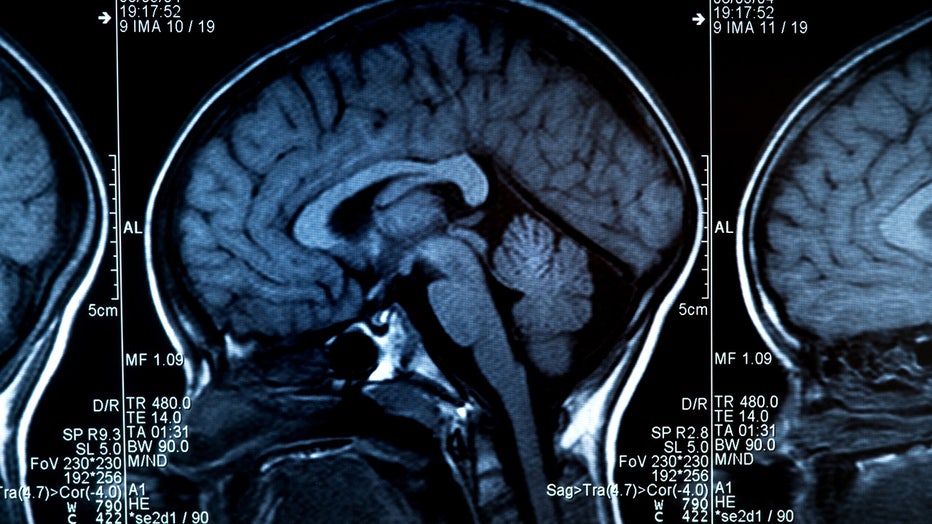

FILE - MRI scan of human brain and skull. (Getty Images)